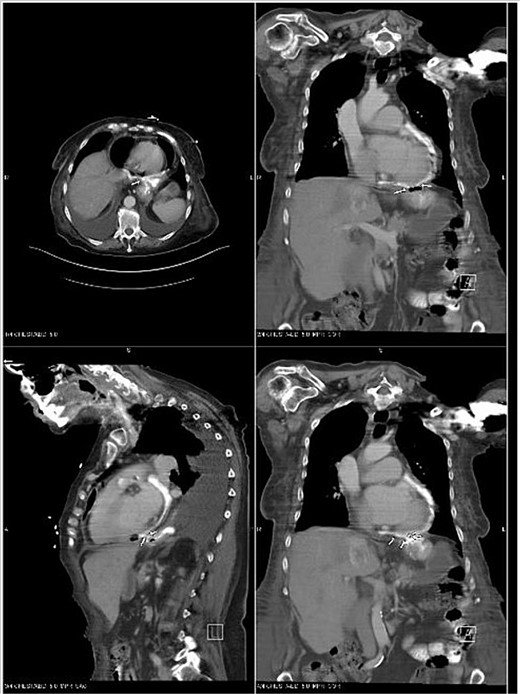

As a part of her workup, it was noted that she had elevated liver function tests, which prompted an abdominal ultrasound that revealed a partially thrombosed portal vein. A follow-up CT of the abdomen and pelvis was then completed. During this CT, the base of the heart was shown to have evidence of pneumopericardium, which led to a CT chest confirming the diagnosis of pneumopericardium with evidence of tamponade (Fig. 1). Tamponade was determined to be primarily contributing to the patient’s hypotension and shock.

CT Abdomen pelvis showing moderate pneumopericardium observable from lower thorax.